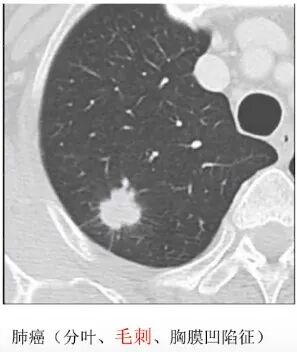

3.3肺结节形态

①持续性肺结节影像学表现为分叶、毛刺、胸膜改变(胸膜牵拉、胸膜皱缩、胸膜附着、胸膜凹陷)、空泡征和血管征(扭曲/扩张/僵硬)及囊腔型等征象者恶性概率高。

②影像学形态如毛刺、分叶、胸膜改变(胸膜牵拉、胸膜皱缩、胸膜附着、胸膜凹陷)、空泡征、血管征(扭曲/扩张/僵硬)及囊腔型等恶性征象者;